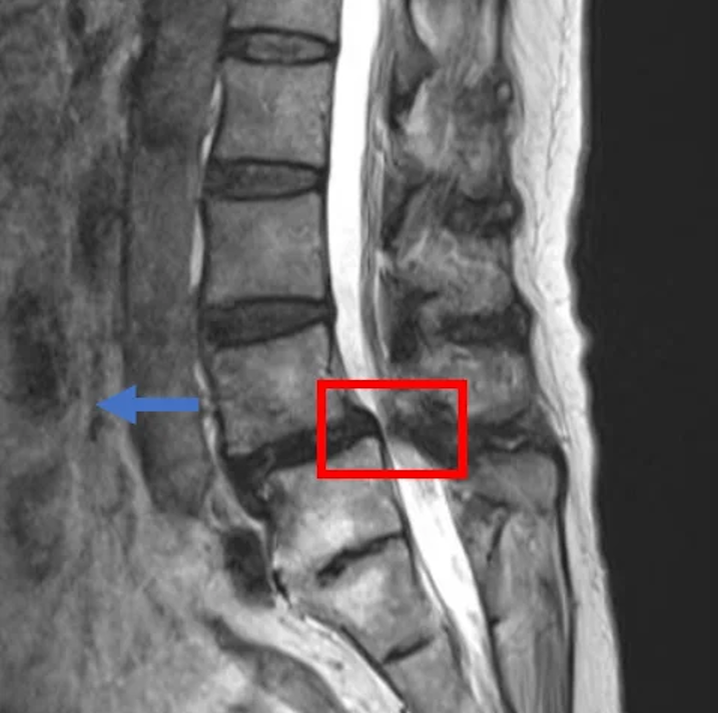

По данным МРТ и результатам осмотра пациентки выявлена протрузия межпозвоночного диска L3/L4, а также спондилолистез и стеноз позвоночного канала на уровне диска L4/L5, сращение позвнков L5 и S1.

В клинике проведена селлгель-терапия на 2 межпозвоночных дисках (L3/L4 и L4/L5).